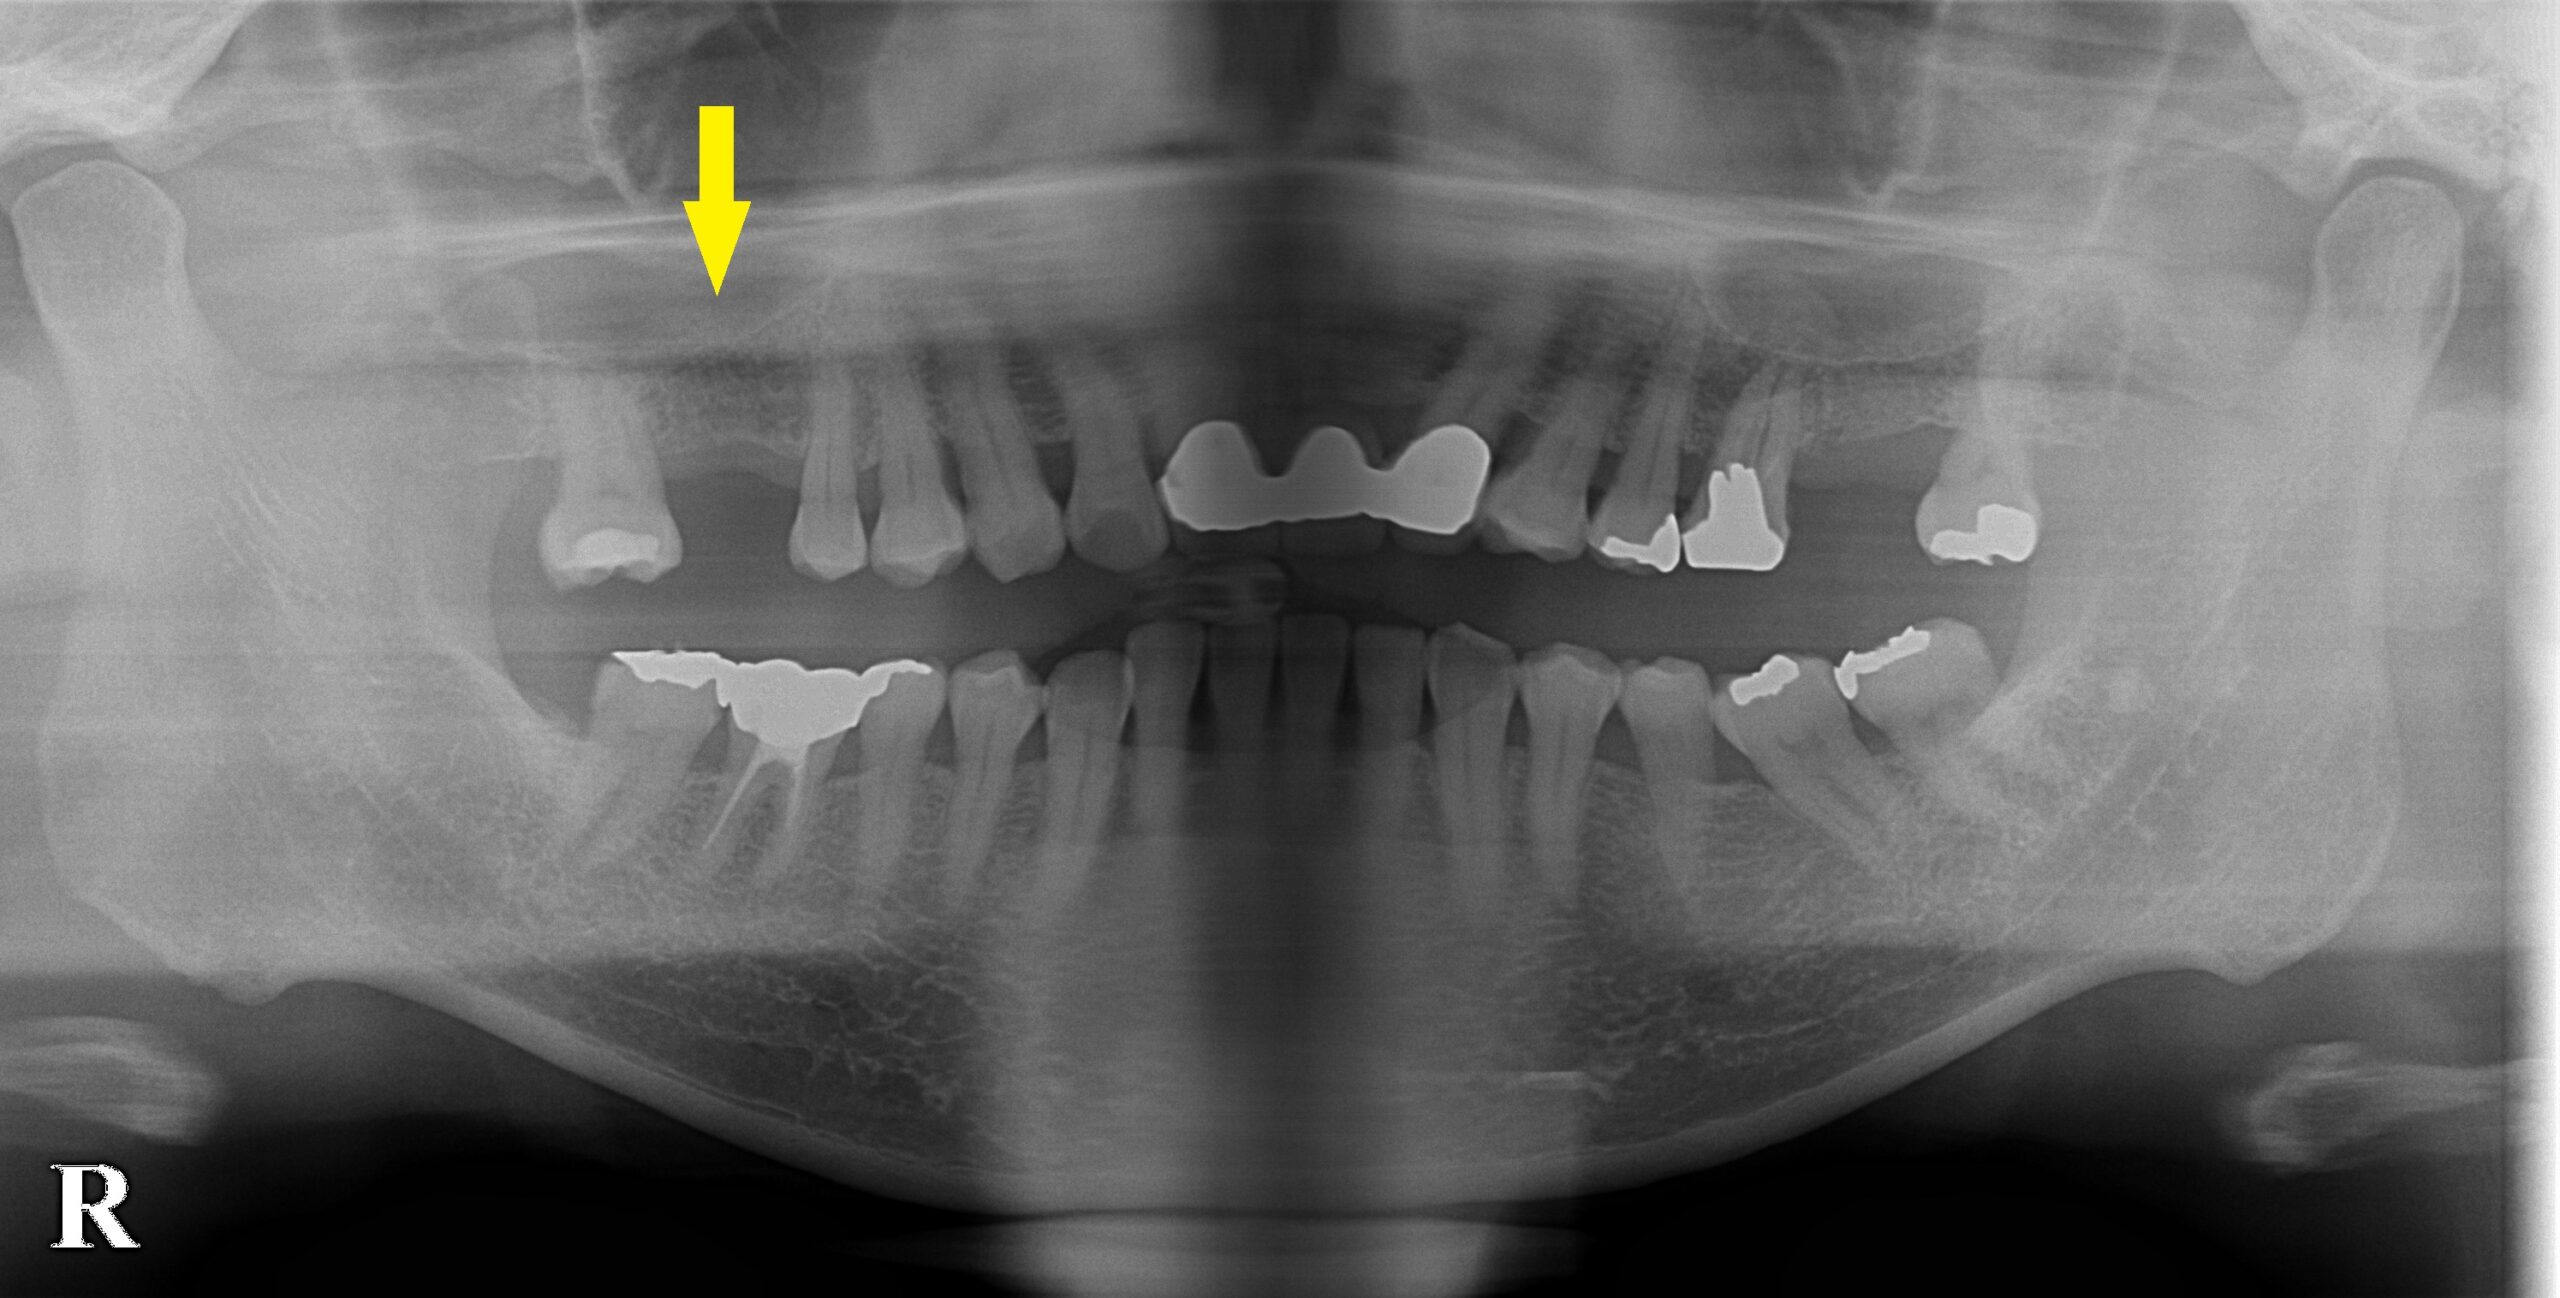

下の写真、上段の単純レントゲン写真では、骨の高さがあるように見えましたが、CTを撮影してみると、下段左の写真のように、骨の形が不整で、インプラントを埋入するには、内側の骨が不足していました。

上顎第一大臼歯の骨造成症例